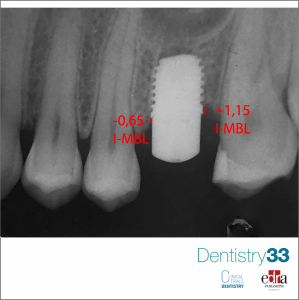

Implantology 13 February 2022

Platform switching vs platform matching: a radiographic analysis of marginal bone loss

Authors: Graziano Montaruli, Susanna Maffione, Giuseppe Troiano, Michele Tepedino, Michele Laurenziello, Luigi Laino, Lorenzo Lo Muzio

A considerable literature claimed that the use of platform switching protocol reduces the exposure of bone crest to the effects of inflammation at implant-abutment junction.The objective of this...